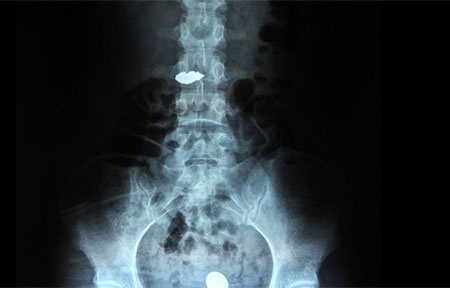

Bé trai 13 tháng tuổi ngậm chiếc nhẫn, nuốt vào dạ dày. Các bác sĩ kịp thời cấp cứu, đưa dị vật ra ngoài.

Bệnh nhi được đưa vào bệnh viện cấp cứu để phẫu thuật nội soi gắp chiếc nhẫn ra ngoài ngay sau đó.

Bệnh nhi vào viện trong tình trạng đau tức ngực, ho nhiều sau khi nuốt nhẫn.